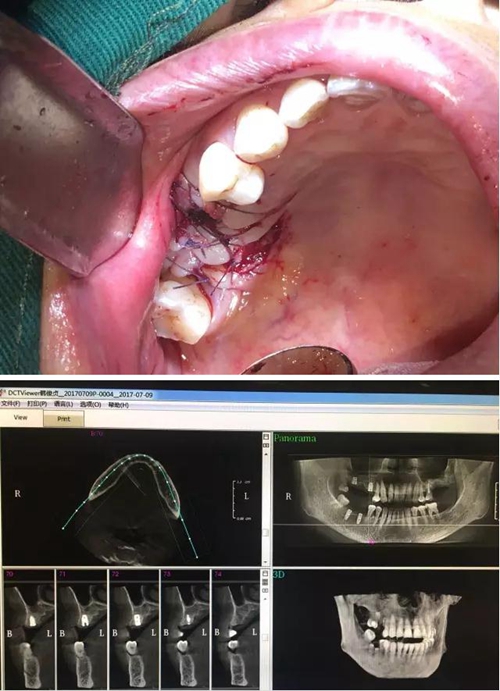

【病例分享】內(nèi)提,用自體骨柱,不用骨粉

3.jpg